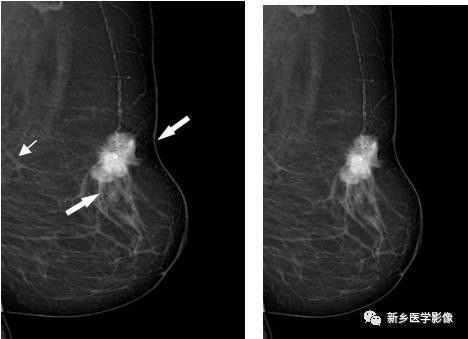

乳腺恶性肿块X线图像

左乳MLO位片示,肿块边缘分叶状,见长短不一毛刺,局部皮肤凹陷(白箭)

左乳MLO位片示,肿块分叶状边缘,周围见透明晕(白箭)